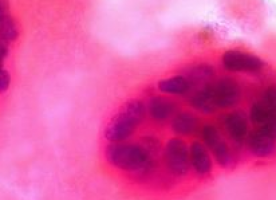

Nilotinib has been designed to be more specific in its binding to the Bcr-Abl kinase domain, of which a genetic mutation of this protein is central to the cause of CML6,7. As a result, nilotinib reduces the rate of progression to more advanced stages of the disease and is proven to generate earlier and higher major molecular response (MMR) rates than the current standard of care, imatinib1,2. Follow-up study results show CCyR, MMR and CMR rates for nilotinib in this patient group continue to be superior to imatinib at 24 months2.